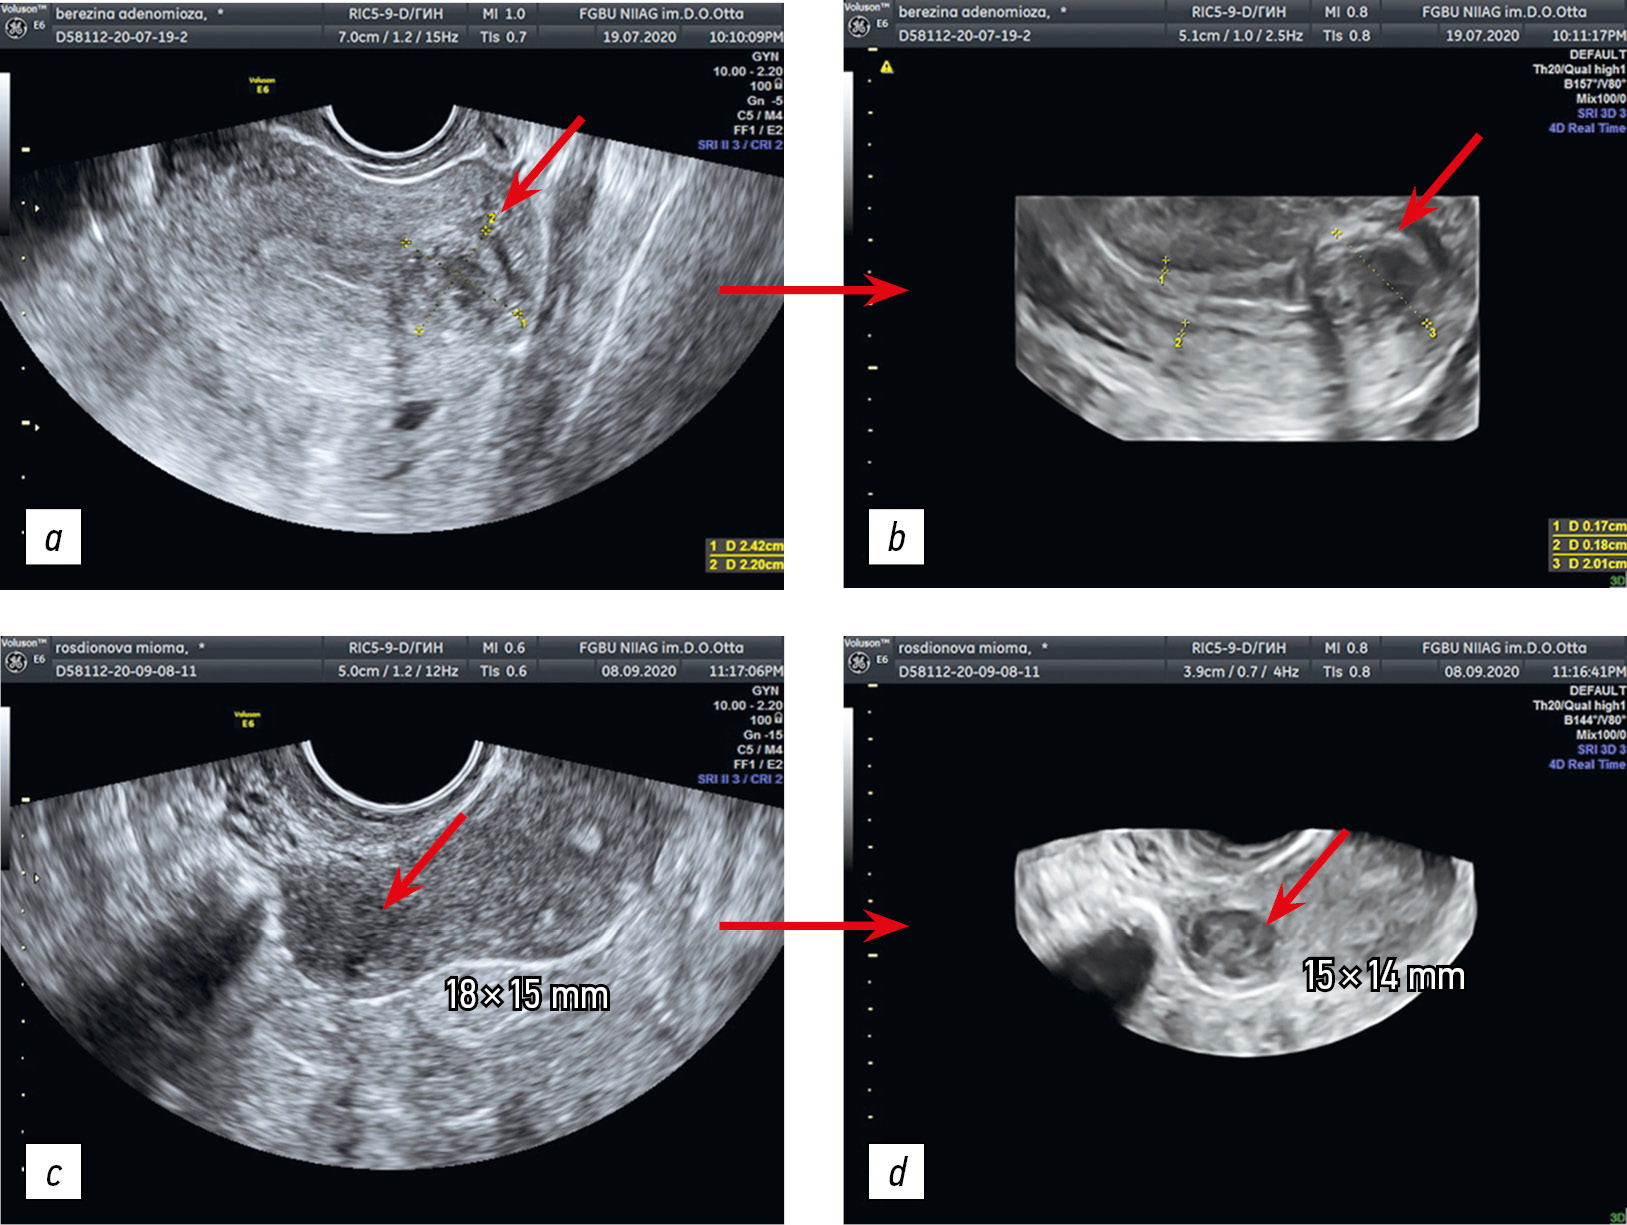

- Ультразвуковое исследование матки в режиме 2D (рис. 3, а, c) Выполнено стандартное ультразвуковое исследование органов малого таза с оценкой наличия аденомиоза по критериям MUSA group. При визуализации узлового образования оценены его эхогенность, размеры, четкость границ, локализация в соответствие с классификацией FIGO. Миоматозные узлы визуализированы в виде округлых гипер- или гипоэхогенных образований в миометрии с относительно четкими границами, в некоторых случаях с акустической тенью. Узлы аденомиоза характеризовались менее четкой визуализацией границ, гипоэхогенной структурой и неправильной формой.

- Ультразвуковое исследование матки в режиме 3D (рис. 3, b, d). После стандартного ультразвукового исследования в двухмерном режиме оценен миометрий в режиме 3D. Миому определяли по наличию четких границ с миометрием, сформированных псевдокапсулой, что позволяло правильно установить ее размеры, которые чаще всего оказывались меньше таковых, измеренных в 2D-режиме (рис. 3, с, d). Размеры и четкость границ узла аденомиоза значимо не изменялись и визуализировались одинаково в режимах 2D и 3D.

Рис. 3. Ультразвуковое изображение миоматозного узла в двухмерном (а, с) и трехмерном (b, d) режимах

Fig. 3. Ultrasound image of the uterine fibroid: (а, c) in 2D mode; (b, d) in 3D mode